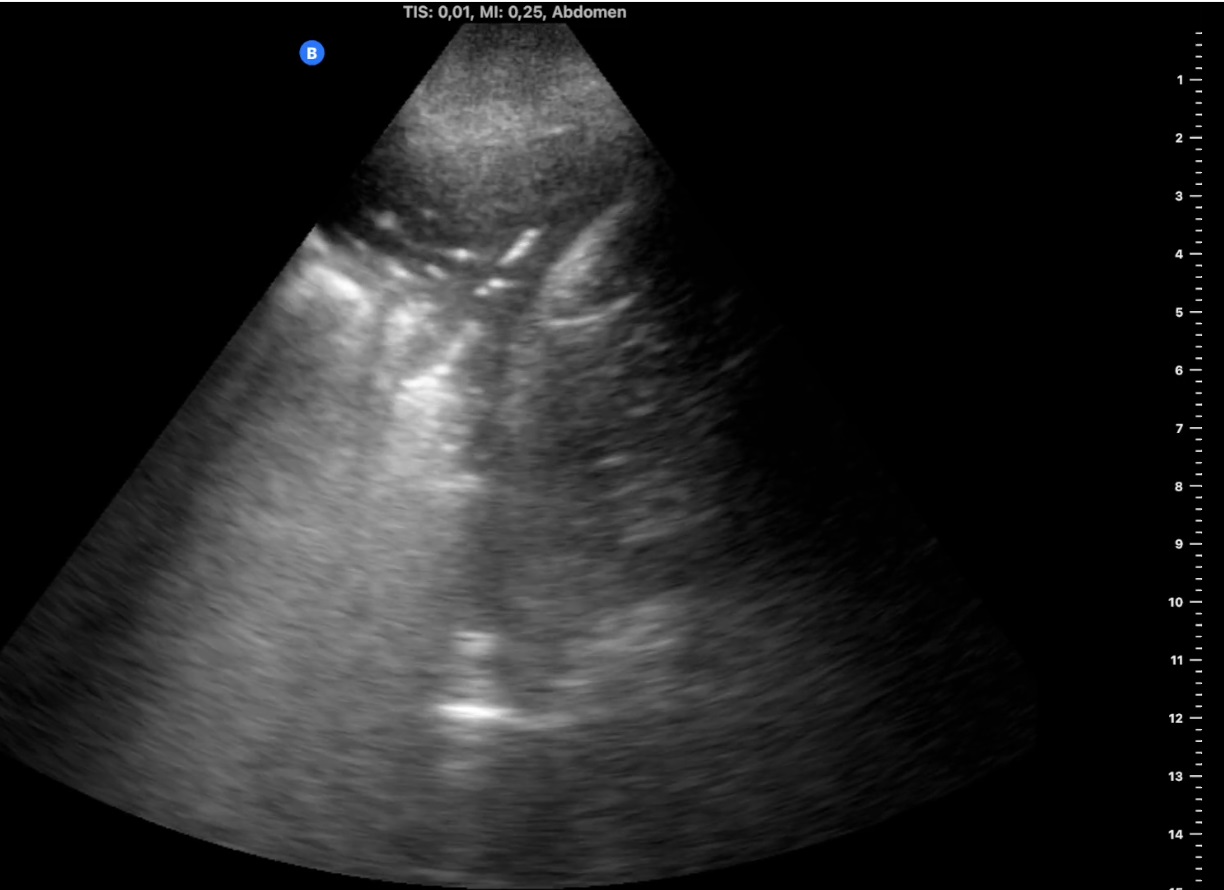

Visita al paciente a los 4 días, manteniendo buen estado general y afebril, con similar imagen ecográfica. Se vuelve a visitar a los 15 días, el paciente está asintomático y en la ecografía ha desaparecido el derrame pleural y la consolidación ha disminuido a 2 x 1,5 cm (imagen 3). A los 2 meses se realiza visita de seguimiento, con mejoría clínica y ecográfica con microconsolidación y líneas B aisladas, pero la familia refiere inflamación desde hace 10 días de la pierna derecha, por lo que se realiza nueva ecografía venosa de MID a nivel inguinal y poplíteo visualizando a este último nivel material ecogénico (imagen 4) y ausencia de compresión. Se inicia tratamiento con heparina a dosis terapéuticas, apoyando el diagnóstico una analítica en domicilio al día siguiente con dímero D de 3769.